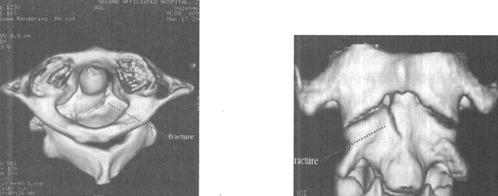

图7-7、图7-8 多排螺旋CT2D重建,显示C2齿状突基底部骨折

图7-9、图7-10 多排螺旋CT3D重建,显示骨折线走行及累及骨表面